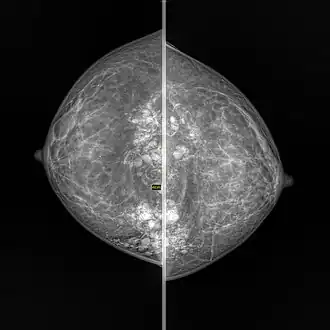

| Snowball like hyperechogenic axillary lymph nodes in a woman with silicone implants removed due to complications | |